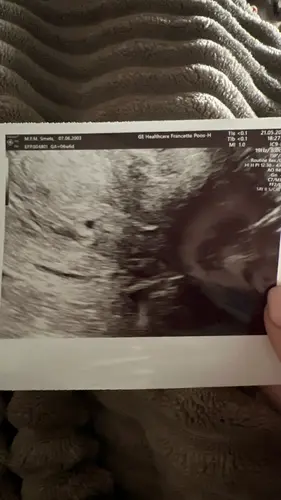

Geen ervaring maar tegen mij zijde ze we plannen je 3 juni in zodat er geen stress ondstaat omdat het wel eens te vroeg kan zijn een echo ik teste met clearblue de 10 de en gaf aan 2 tot 3 weken ... misschien hebben ze gewoon te vroeg de echo gedaan liefs mon

Ik hoop inderdaad dat het gewoon te vroeg was. Ik heb van iemand anders ook al gehoord dat ze de 12e 2-3 weken had op de clear blue test.

Hi lieverd als je 16 januari ongeveer bent uitgerekend zit je oo 5.6 ongeveer ik ben 10 januari uitgerekend en ben vandaag 6.5 weken hoop dat dit je ook iets meer geruststelt?